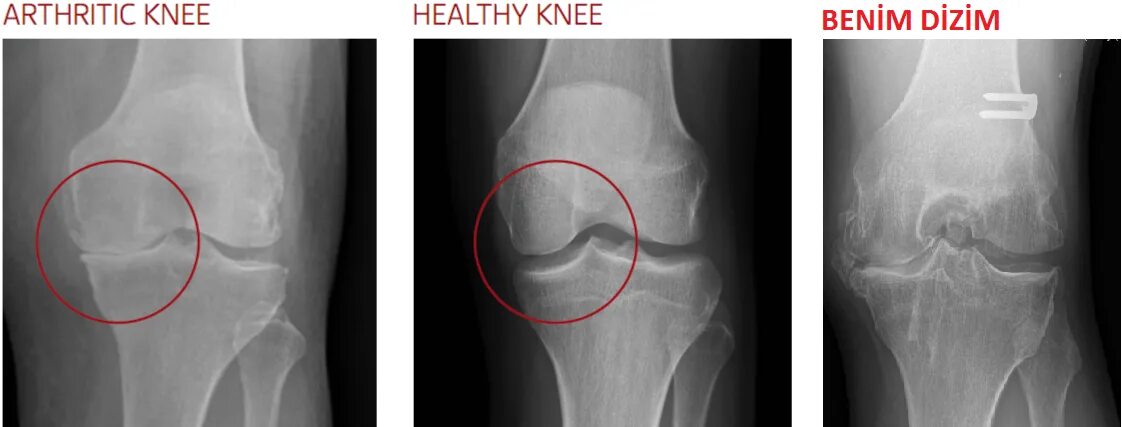

Рентгенография коленного сустава 2 проекции